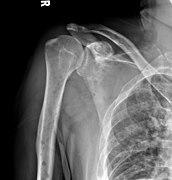

Medical imaging

The diagnostic examination of a person with suspected multiple myeloma typically includes a skeletal survey. This is a series of X-rays of the skull, axial skeleton, and proximal long bones. Myeloma activity sometimes appears as "lytic lesions" (with local disappearance of normal bone due to resorption). And on the skull X-ray as "punched-out lesions" (pepper-pot skull). Lesions may also be sclerotic, which is seen as radiodense.[52] Overall, the radiodensity of myeloma is between −30 and 120 Hounsfield units (HU).[53] Magnetic resonance imaging is more sensitive than simple X-rays in the detection of lytic lesions, and may supersede a skeletal survey, especially when vertebral disease is suspected. Occasionally, a CT scan is performed to measure the size of soft-tissue plasmacytomas. Bone scans are typically not of any additional value in the workup of people with myeloma (no new bone formation; lytic lesions not well visualized on bone scan).